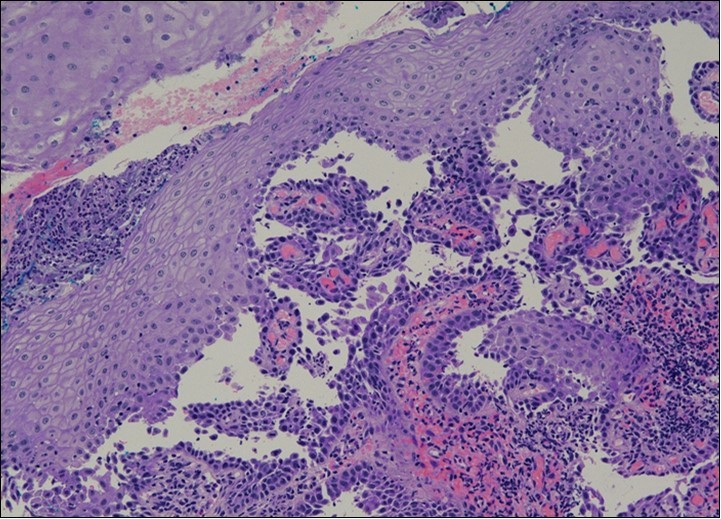

HPV test was negative for high risk subtypes of HPV. The punch biopsy specimen comprised a piece of inflamed cervical tissue in which the transformation zone was represented. The cervical tissue was covered by metaplastic and hyperplastic squamous epithelium showing intraepidermal suprabasal blister formation with acantholysis. Well vascularised dermal papillae lined residual basal cells giving rise to a tombstone appearance were present. There was no evidence of HPV, CIN, CGIN or invasive malignancy.

She was discussed at the hospital cyto-pathology conference to clarify the diagnosis. The original cytological smear specimen was reviewed, with features of bi-nucleation and koilocytosis consistent with LSIL. The cervical biopsy was also reviewed, confirming typical features suggestive of cervical pemphigus. (Figure 4a, Figure 4b, Figure 4c)

Figure 4a.Cervical tissue showing intraepidermal and supra-basal blister formation.

Figure 4b.Prominent acantholysis identified

Figure 4c.Well vascularised dermal papillae with residual basal layer giving rise to tombstone appearance